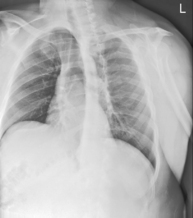

• Erect, chin raised, hands on hips with palms out, roll shoulders forward

• Center CR to T7 region. Top of IR will be approximately 2″ (5 cm) above shoulders on average patient.

• Center thorax bilaterally to IR borders with equal margins on both sides; ensure there is no rotation of thorax.